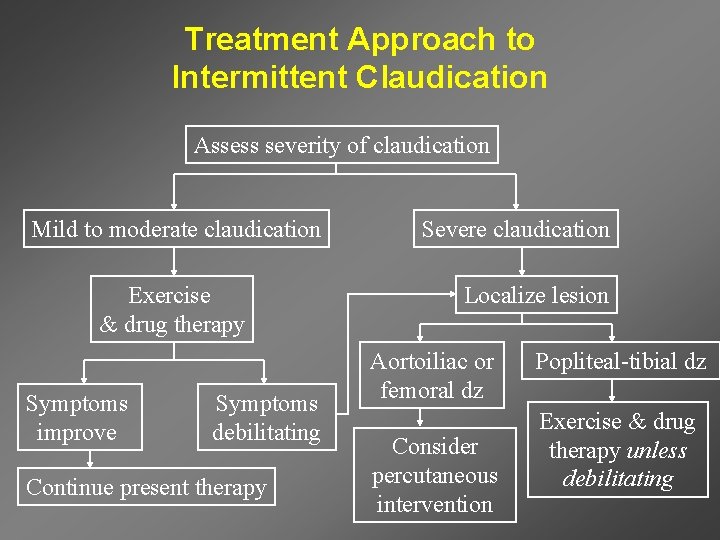

Treatment Approach to Intermittent Claudication Assess severity of claudication Mild to moderate claudication Exercise & drug therapy Symptoms improve Symptoms debilitating Continue present therapy Severe claudication Localize lesion Aortoiliac or femoral dz Consider percutaneous intervention Popliteal-tibial dz Exercise & drug therapy unless debilitating